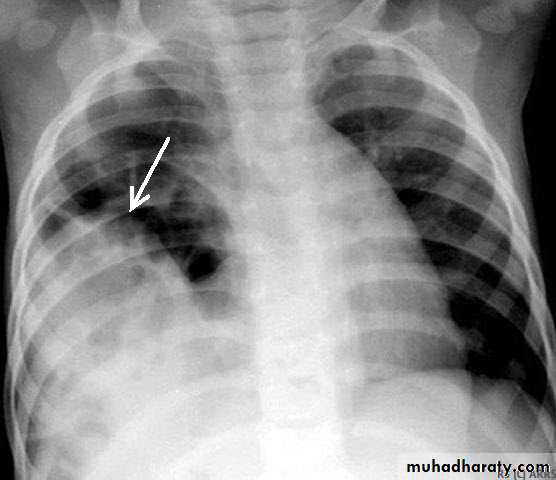

X-ray pneumothorax